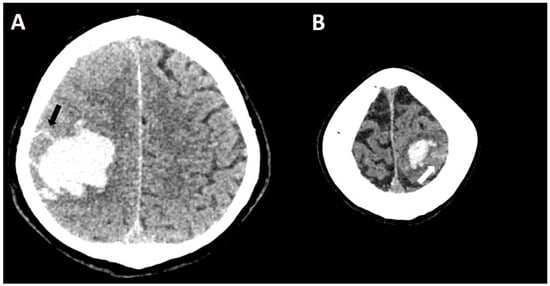

6.1. Finger-like Projections

6.2. Subarachnoid Extension of Lobar Hemorrhage

- Renard, D.; Parvu, T.; Thouvenot, E. Finger-Like Projections in Lobar Haemorrhage on Early Magnetic Resonance Imaging Is Associated with Probable Cerebral Amyloid Angiopathy. Cerebrovasc. Dis. 2019, 47, 121–126. [Google Scholar] [CrossRef]

- Baron, J.-C.; Boulouis, G.; Benzakoun, J.; Schwall, C.; Oppenheim, C.; Turc, G.; Varlet, P. Cerebral amyloid angiopathy-related acute lobar intra-cerebral hemorrhage: Diagnostic value of plain CT. J. Neurol. 2022, 269, 2126–2132. [Google Scholar] [CrossRef]

- Renard, D.; Parvu, T.; Tatu, L.; Thouvenot, E. Subarachnoid extension of lobar hemorrhage on acute/subacute MRI is associated with cerebral amyloid angiopathy criteria. Acta Neurol. Belg. 2020, 120, 863–866. [Google Scholar] [CrossRef]

- Baron, J.-C.; Jensen-Kondering, U.; Sacco, S.; Posener, S.; Benzakoun, J.; Pallud, J.; Oppenheim, C.; Varlet, P.; Turc, G. Can novel CT-and MR-based neuroimaging biomarkers further improve the etiological diagnosis of lobar intra-cerebral hemorrhage? J. Neurol. 2023, 270, 582–588. [Google Scholar] [CrossRef]